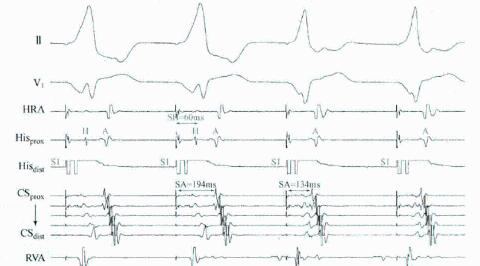

<p>关于图中VOP描述错误的是&#xff1f;</p>

关于图中VOP描述错误的是?

心房仍然是心动过速的频率

一定是AT

出现了室房分离的现象

说明心动过速和心室无关